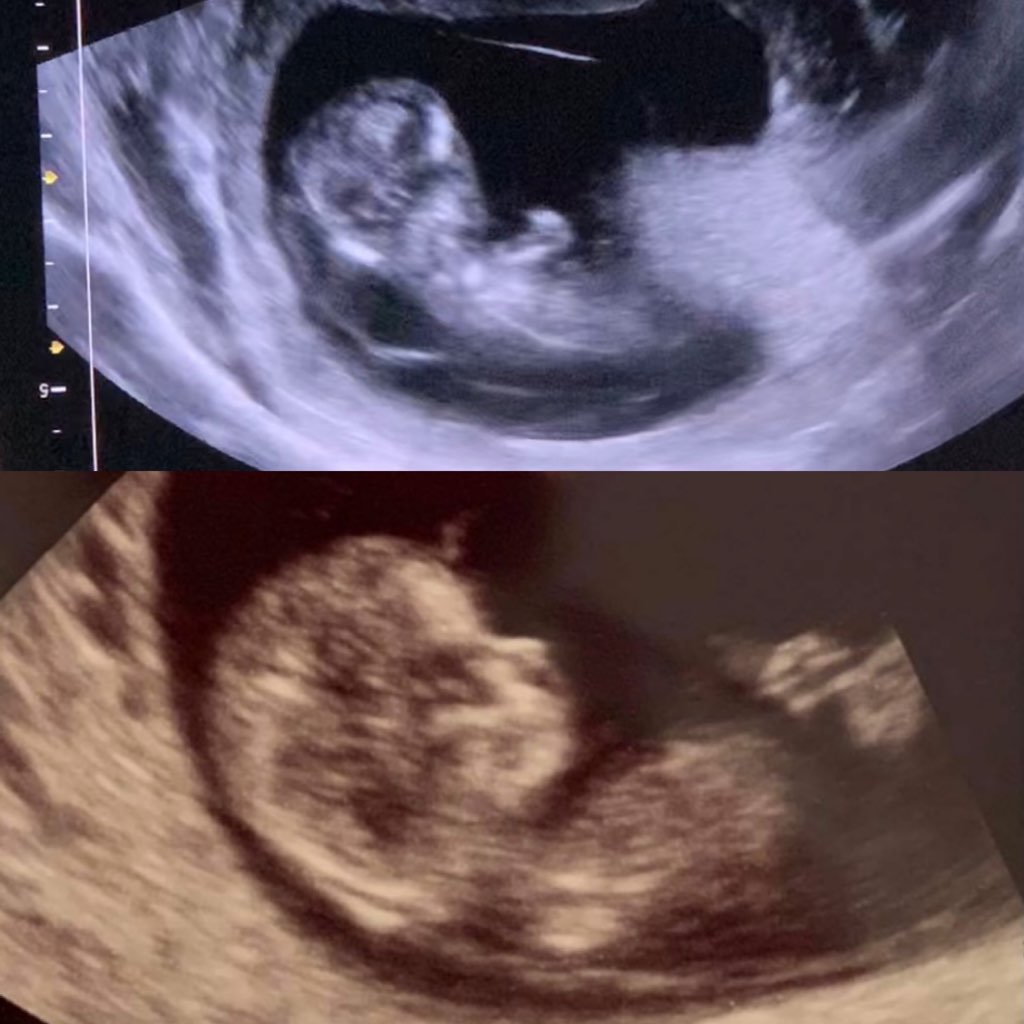

Pierwsze usg 11+4 2,70cm

Drugie (obecnie) 10+0 3,5cm

Pierwsza widoczna różnica to budowa głowy.

Druga to NT (przeziernosc karkowa czyli fałd skórny nad karkiem wypleniony płynem). Pierwsza ciąża 10mm, obecnie wizualnie wyglada na prawidłowe czyli poniżej 2,5mm.

Pierwsza ciąża brak kości nosowej, obecnie już w 10 tygodniu piękny nosek.